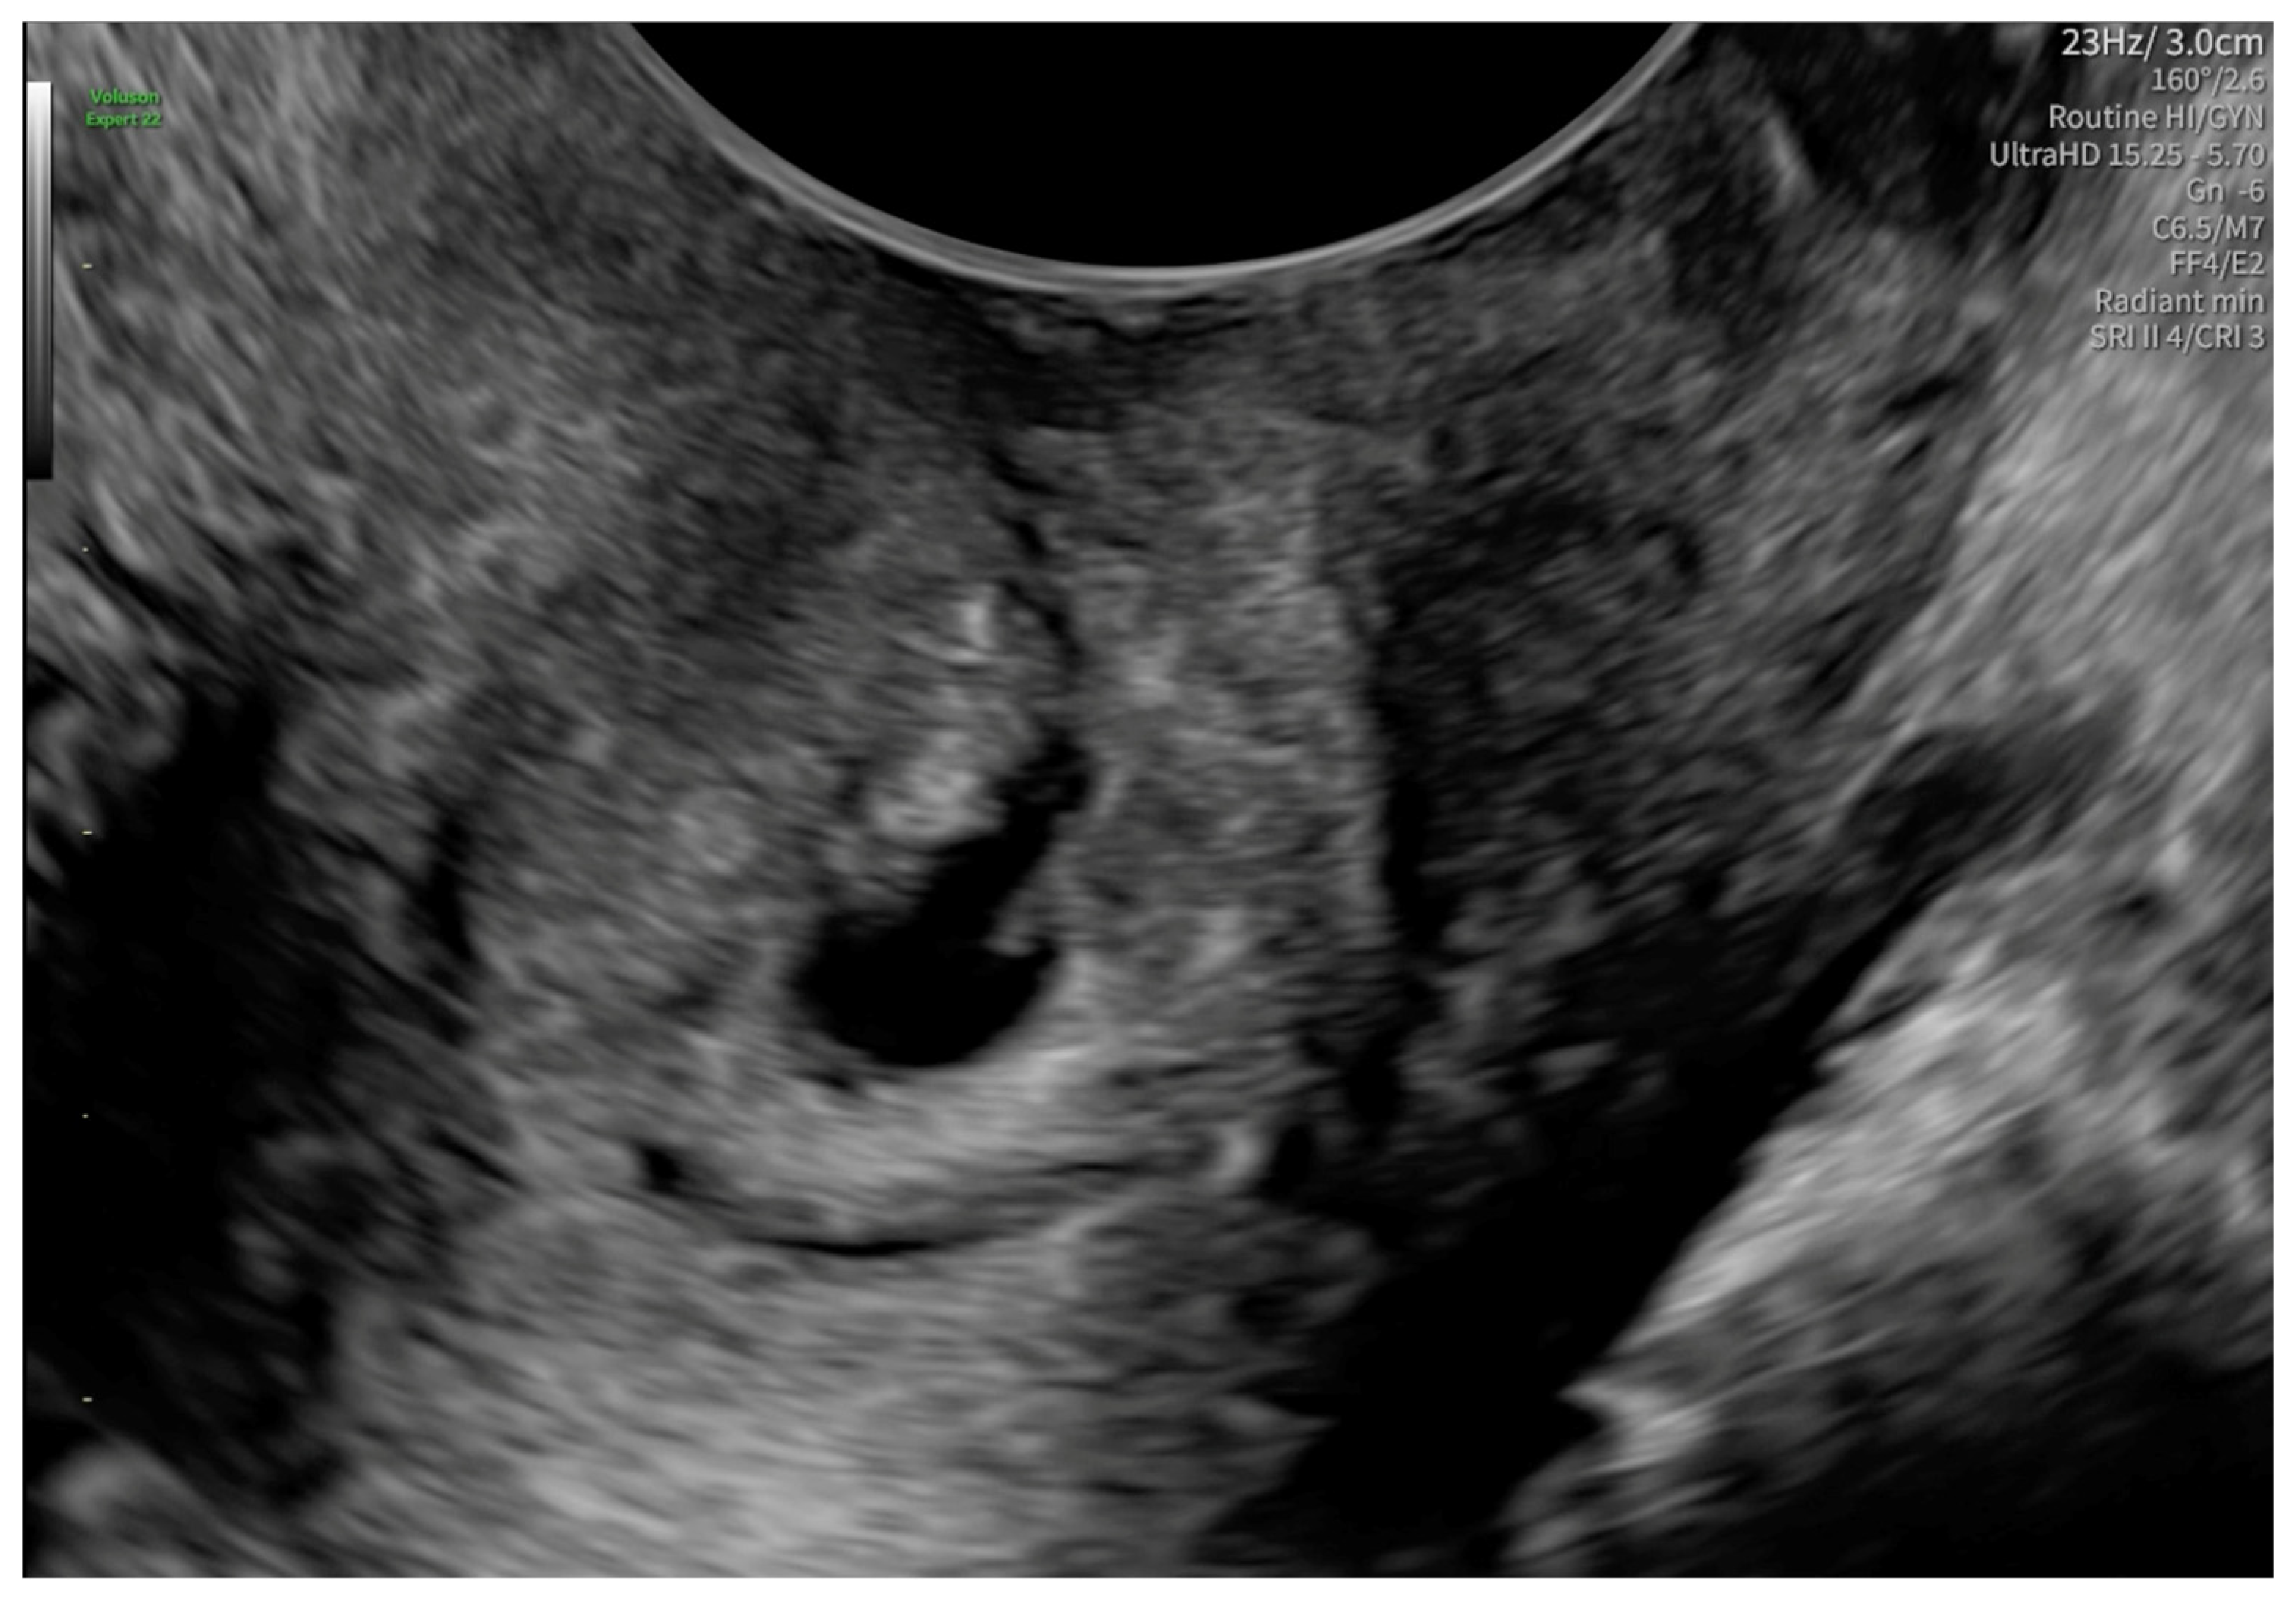

2. Case Presentation